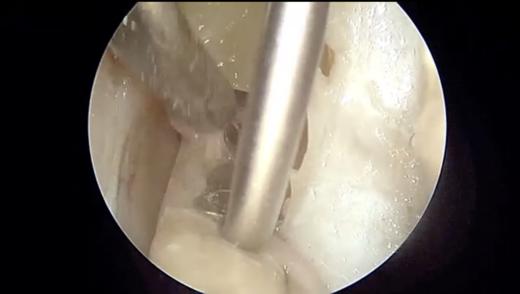

标本的内听道解剖训练视频2